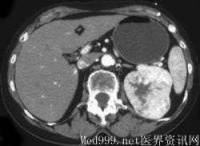

4.CT检查示肾内实质性占位性病变及CT值低的脂肪成份。

cm,病程1个月~7年。主要临床症状为腰部不适、胀痛、包块、出血性休克等。22例均行KUB加IVP和CT检查,2例行MRI检查。IVP表现为正常或提示肾盂肾盏受压变形;B超检查多表现为强回声光团,也表现为混合回声,诊断准确率为86.4%(19/22);CT平扫多表现为圆形或类圆形低密度或极低密度病灶,病灶位于肾实质内或突出于肾轮廓外,诊断准确率为90.9%(20/22)。

的良性肿瘤,由于肾基质缺乏脂肪和平滑肌,故通常认为属错构瘤。有20%肾错构瘤合并节结性硬化症,并双侧同时发生,病变较小,常并发癫痫、智力低下、面部皮脂腺瘤等。肾错构瘤以中年女性为多见。陈承志等报告男女比例为1∶2.25,本组为1∶1.2。 B超结合CT诊断肾错构瘤有重要价值,随着超声、CT和MRI的应用,肾错构瘤的发病率有所增加,术前诊断准确率也有所提高。肾错构瘤与肾细胞癌影像学鉴别要点在于肾错构瘤含有较多脂肪成分而正常肾及肾细胞癌组织极少或没有,肾错构瘤在B超图像中表现为强回声光团,偶然可见混合性低回声。CT显示比超声图像更敏感,CT值于小-10Hu,因此,典型的肾错构瘤不难诊断。MRI检查时,T1加权像较低,T2加权像又极高。IVU主要了解双肾功能情况,对于评估肾功能不良患者是否进行手术以及手术方式的选择具有重要作用。